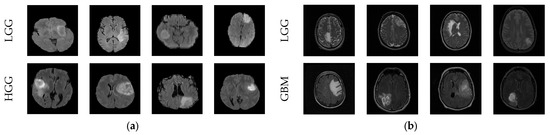

3.2. MRI Dataset